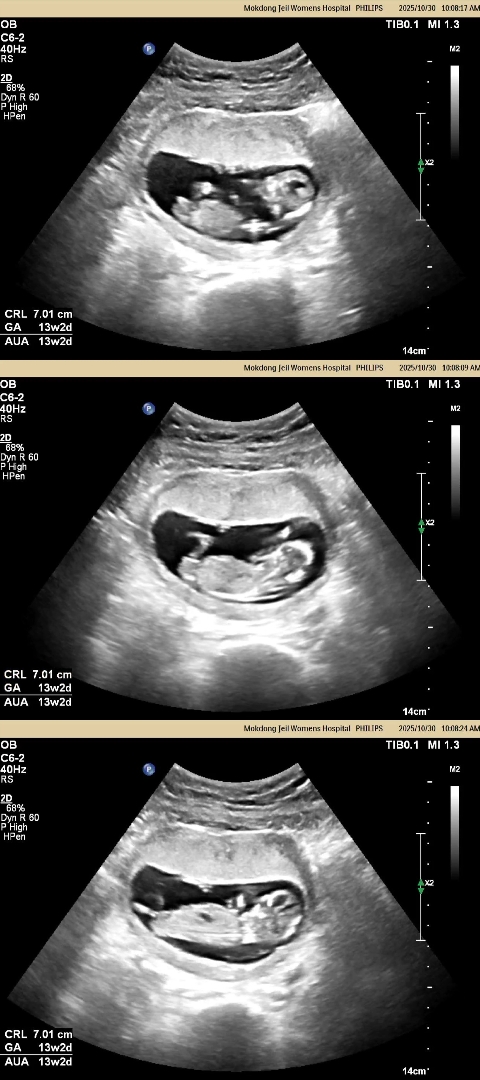

고수님들~ 많이봐주세용 성별♡

니프티 하고왔고, 성별 상관없는데 기다리면서 너어어무 궁금해서 못참겠어요 ㅋㅋㅋㅋ 혼자 30번은 돌려본거같은데, 긴가민가?! 고수님들이 보시기에는 어떠신가요?!